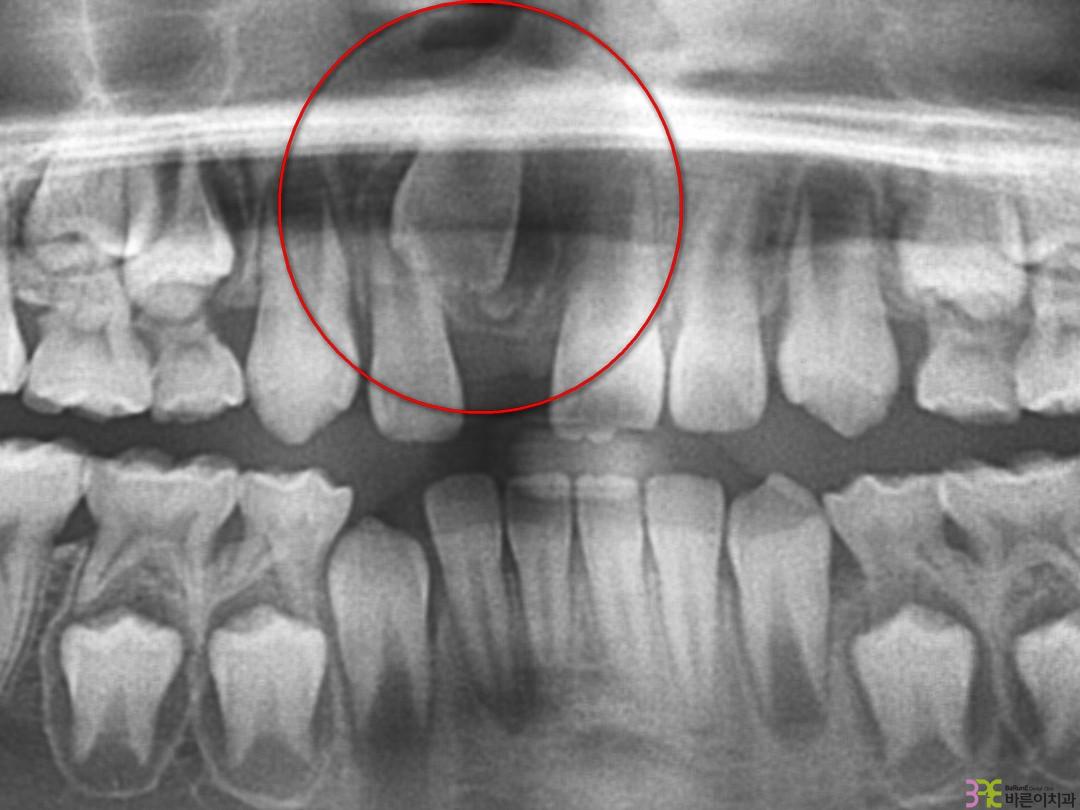

치료명

매복치 교정

치료기간

8개월

Before

After